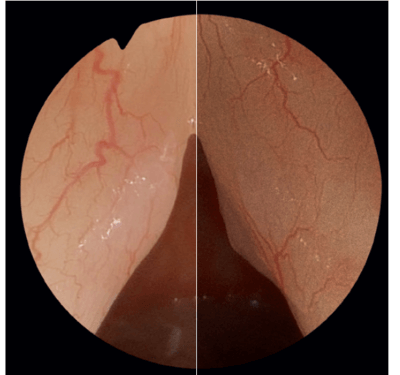

ED Glass Lenses – Razor-Sharp Images

Right: Normal Glass Lenses

- Optimized for high-resolution imaging

- Decreased chromatic aberration

- High contrast at high spatial frequencies